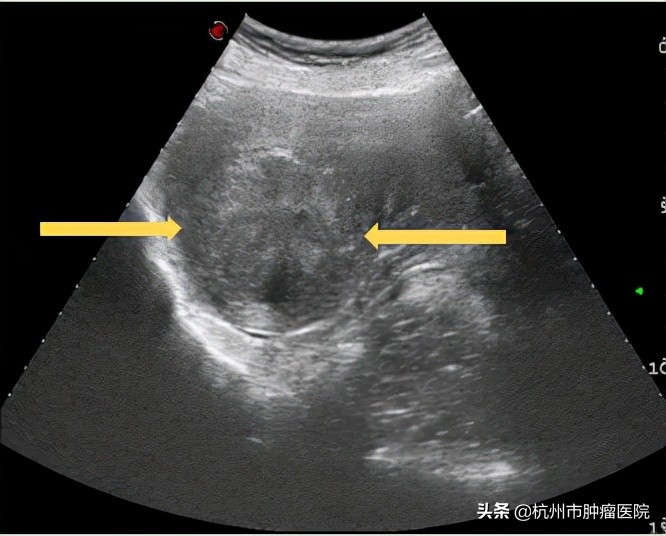

子宫肌瘤术前超声

超声影像科雷志锴主任对章女士进行了详细的超声检查及磁共振检查,均提示有多发性子宫肌瘤,其中最大一枚大小约5.3x4.2x4.5cm,且与子宫内膜关系密切。雷主任经过详细评估,考虑章女士是由子宫肌瘤导致月经量增多引起贫血。结合章女*的年士**龄、病情等因素,雷志锴主任建议她行超声引导下子宫肌瘤微波消融术。